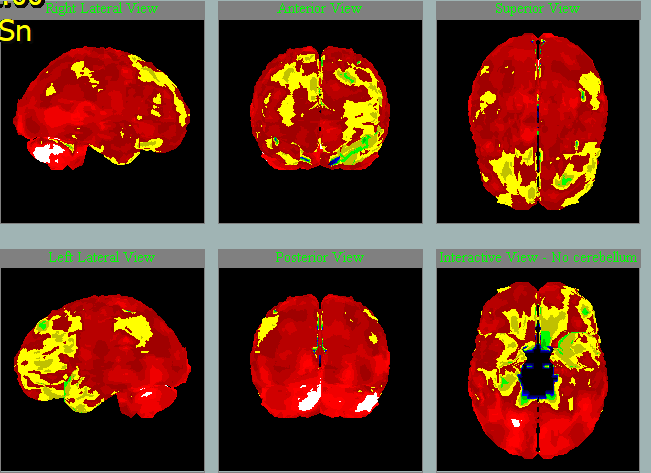

Nemoc s Lewyho tělísky

SPECT mozku u pacientky a její dcery

dcera, 54 let, VŠ

matka, 82 let

Hledejte ne 5 rozdílů, ale v čem se oba mozky podobají….